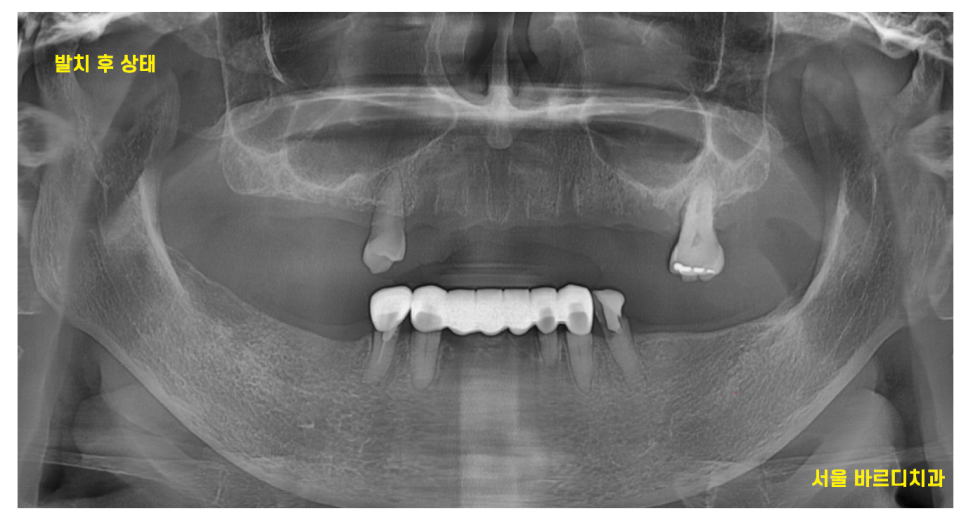

23.10.10

예후가 좋지 않은 치아는

발치를 하고

뼈가 차기를 기다리며

아래 앞니를 치료한 사진입니다.

환자분께서는 어떻게 치료해야할지 고민이 많으셨는데

그동안은 임시틀니를 사용하며 지내셨어요~